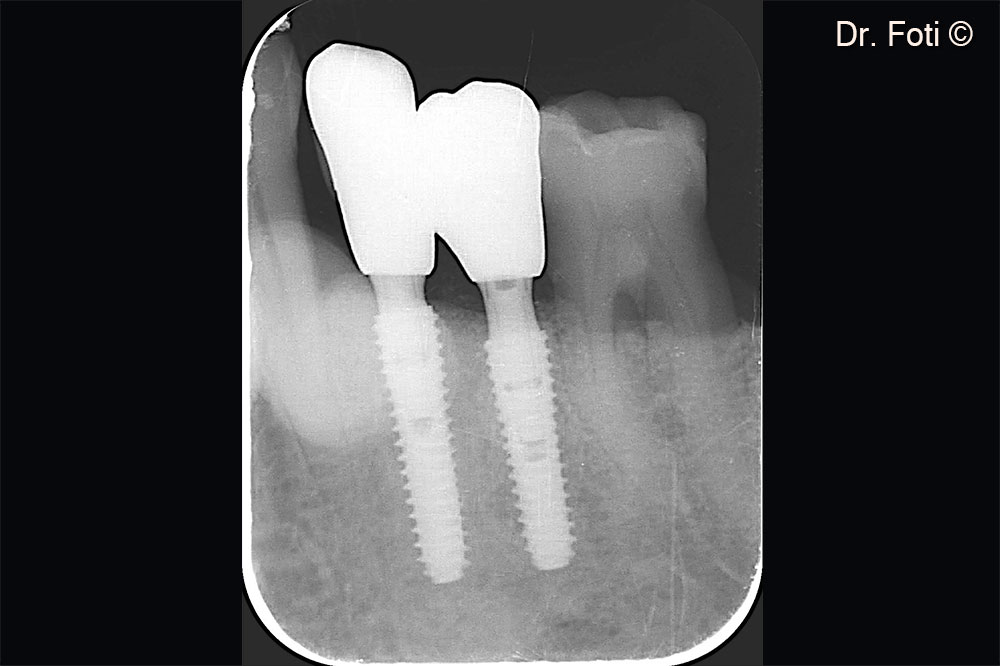

The follow-up radiograph shows newly formed bone between the canine and implant in position 34